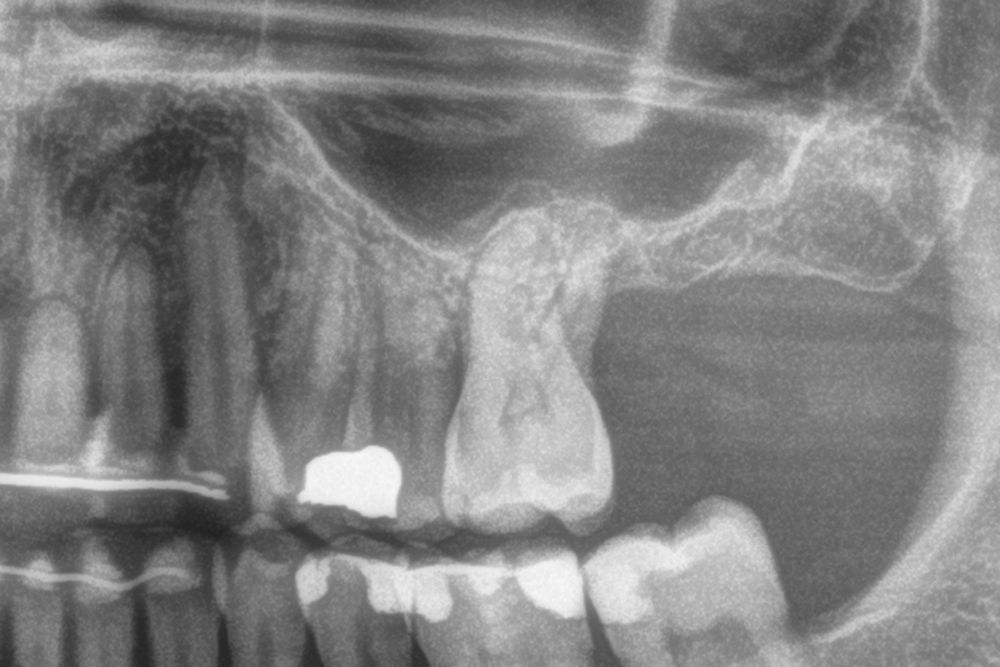

Figures 2-19 show one of the cases included in the study.

In all cases, a diagnosis was made based on study models, intraoral examination of the patient and performing a Cone-beam analysed using the specific BTI-Scan 3 software (Biotechnology Institute, Vitoria, Alava, Spain).

Patients attend subsequent check-ups performing a control Cone-Beam after 5 months (before loading the implant) and after one year of the load, performing a new measurement in these images to analyse the bone gain and the maintenance of the same. In these check-ups, data are collected on prosthetic complications or crestal bone loss in these patients, as well as possible failures.